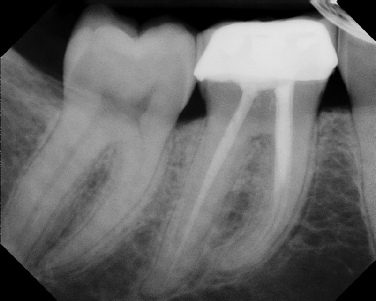

Root Canal Retreatment - Meriden 8 mos. recall Post-op Pre-op